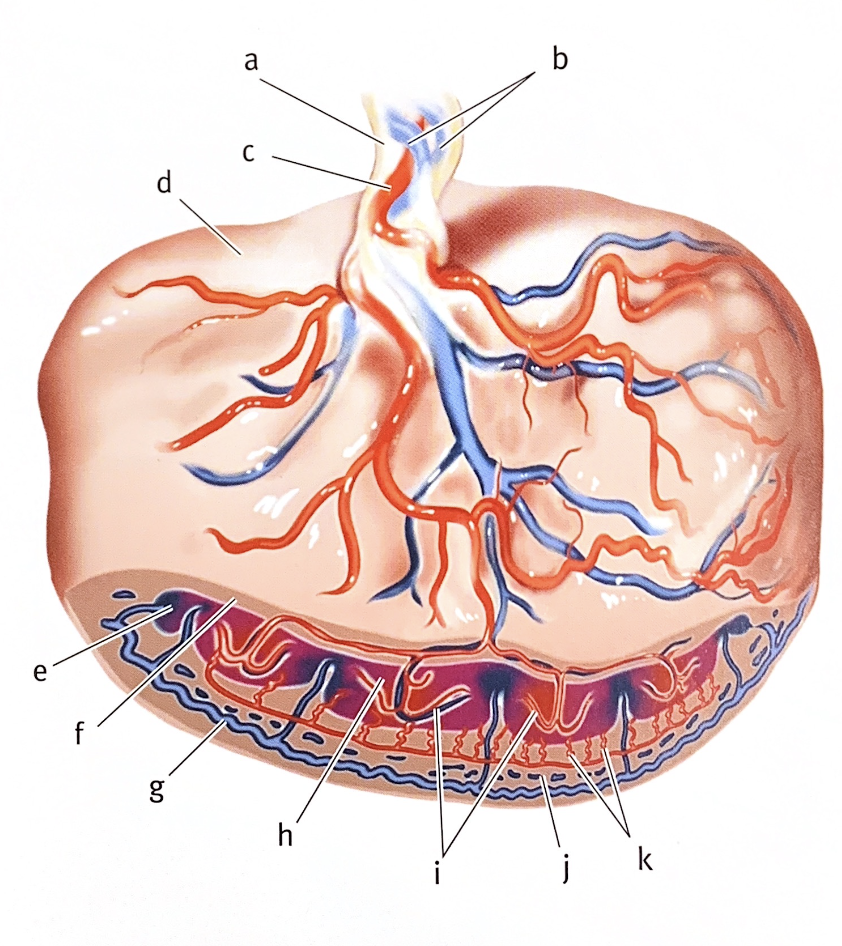

The placenta is a materno-fetal organ which begins developing at implantation of the blastocyst and is delivered with the fetus at birth. The placenta is unique because it develops from two separate individuals, the mother and the fetus. By the beginning of the twelfth week, the placenta has two distinct parts:

a. the fetal portion formed by the chorionic villi and

b. the maternal portion formed by part of the endometrium of the uterus.

Anatomical features :-

- Shape: Circular, disc shape.

- Size-15-20 cm in diameter.

- Thickness: 2.5 cm at the centre but thins off towards the periphery.

- Weight: 500-600 gm (approximately).

- Covers-30% of the uterine wall.

- Surface-Fetal surface and maternal surface.